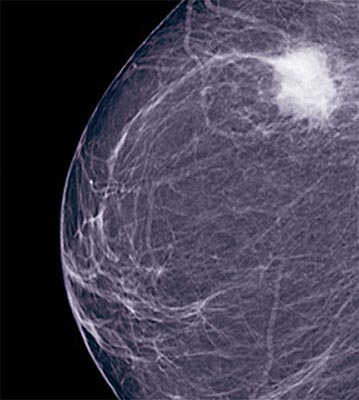

While thermography has been around for more than half a century, it has been put to medical use, especially breast cancer detection much later. FDA has stated that it is not as effective as mammogram in detecting breast cancer at an early stage. Therefore it must not be used instead of mammogram. The thermal imaging process does not involve any invasive, painful procedures or any risks associated with radiation. Thermography can detect more metabolically active areas as there is increased blood flow to that area. It is used in the case of fibrocystic breast disease, mastitis and cancer risk. This is because cancer tissue is more metabolically active.